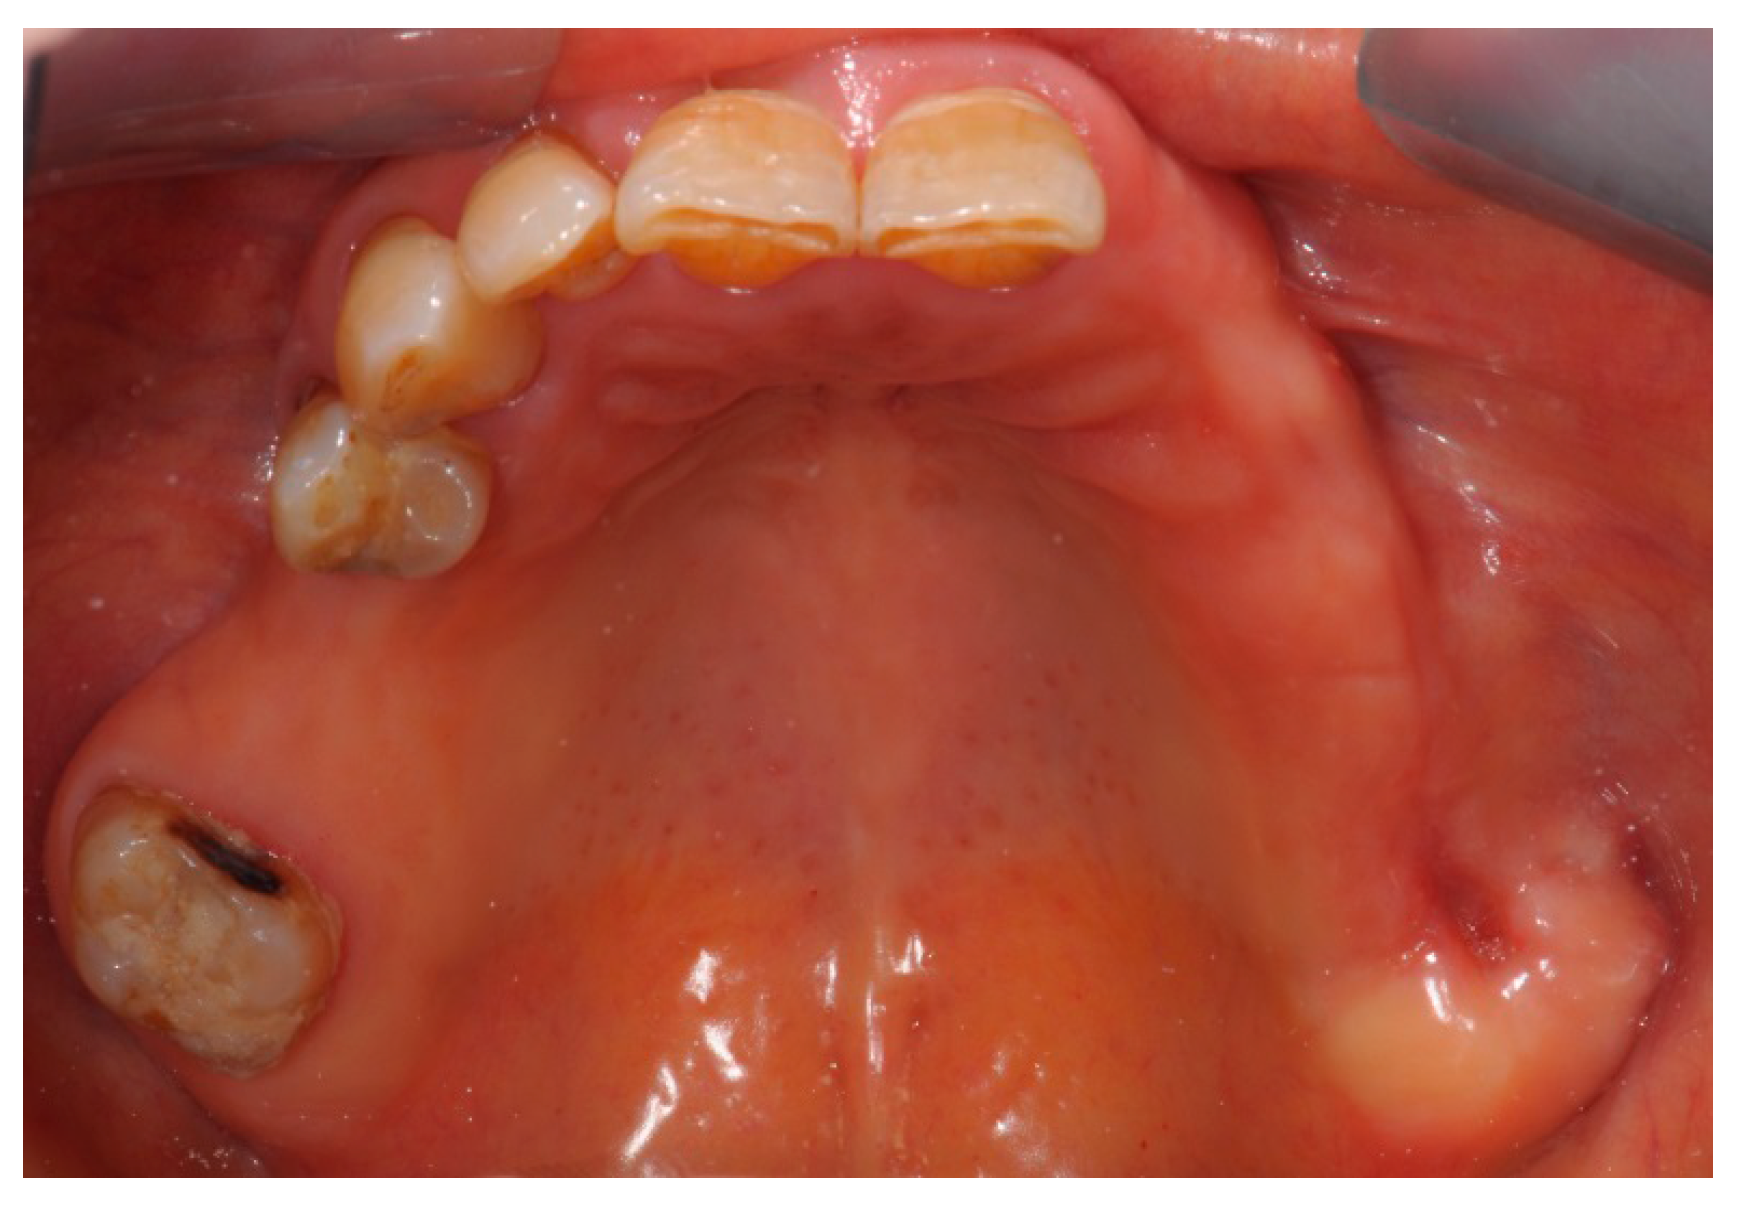

2. Case Report